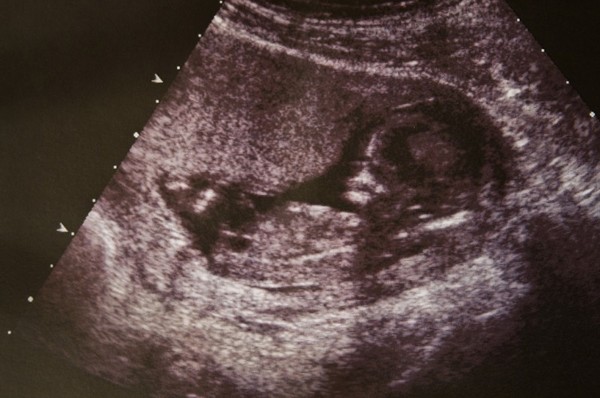

Bebekte Su Toplanmasi Ultrason Klinik